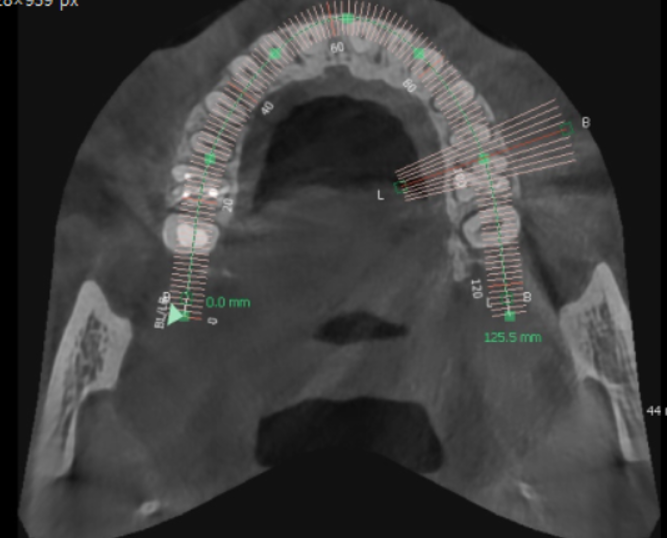

디지털 임플란트 시에는 ct 장비를 통해 분석을 하고

수술에 들어갑니다.

- 분석 > 수술

또한 임플란트가 들어갈 위치

식립 각도를 예측하여 개인 맞춤형 수술을 진행하였습니다.

위에 환자분은 잇몸 뼈가 부족하여

상악동을 들어 올리고 뼈이식을 하셔야 하는 환자분이었는데요

개인별로 다른 구강환경을 분석하여 미리 예측

잇몸도 최소로 절개할 수 있고

미리 분석한 자료를 토대로 30분 이내의 빠른 수술이 가능했습니다.